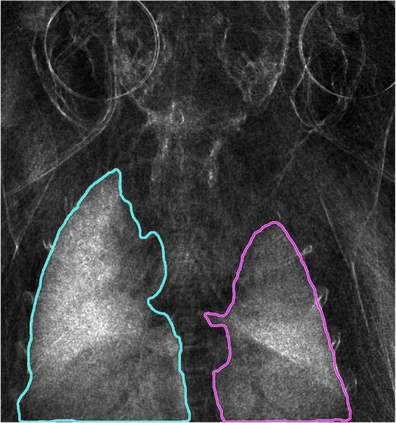

Low-dose computed tomography (LDCT) is the current standard for lung cancer screening, yet its adoption and accessibility remain limited. Many regions lack LDCT infrastructure, and even among those screened, early-stage cancer detection often yield false positives, as shown in the National Lung Screening Trial (NLST) with a sensitivity of 93.8 percent and a false-positive rate of 26.6 percent. We aim to investigate whether X-ray dark-field imaging (DFI) radiograph, a technique sensitive to small-angle scatter from alveolar microstructure and less susceptible to organ shadowing, can significantly improve early-stage lung tumor detection when coupled with deep-learning segmentation. Using paired attenuation (ATTN) and DFI radiograph images of euthanized mouse lungs, we generated realistic synthetic tumors with irregular boundaries and intensity profiles consistent with physical lung contrast. A U-Net segmentation network was trained on small patches using either ATTN, DFI, or a combination of ATTN and DFI channels.Results show that the DFI-only model achieved a true-positive detection rate of 83.7 percent, compared with 51 percent for ATTN-only, while maintaining comparable specificity (90.5 versus 92.9 percent). The combined ATTN and DFI input achieved 79.6 percent sensitivity and 97.6 percent specificity. In conclusion, DFI substantially improves early-tumor detectability in comparison to standard attenuation radiography and shows potential as an accessible, low-cost, low-dose alternative for pre-clinical or limited-resource screening where LDCT is unavailable.